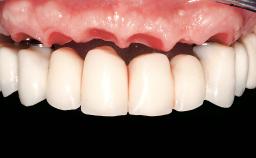

A 65-year-old female patient with a failing residual maxillary dentition and a complete mandibular removable denture was referred for consultation and treatment. The patient’s chief complaint was that her upper residual teeth were mobile and she was unable to chew. The patient also asked us to improve the esthetic appearance of her smile. The patient’s desire was a stable and comfortable dentition in both jaws, and she specifically asked for a fixed rehabilitation. The patient reported a history of recurrent caries, endodontic complications, and periodontal disease as main reasons for previous teeth extractions. The anamnesis was negative for bruxism and TMJ disorders. The patient had no systemic diseases, was not on any medication,and did not smoke. The extraoral examination revealed a medium lip line, a wide diastema between the two central incisors (which, according to the patient, had appeared recently), and a partial collapse of the perioral soft tissues, probably due to loss of the correct vertical dimensions.